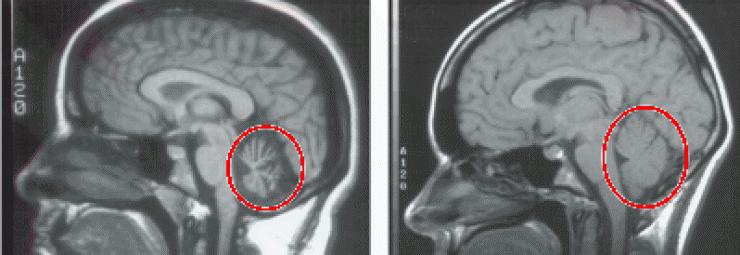

跨越20余年的全脑干和小脑萎缩——病因? - 神经科学专业讨论版 -丁香